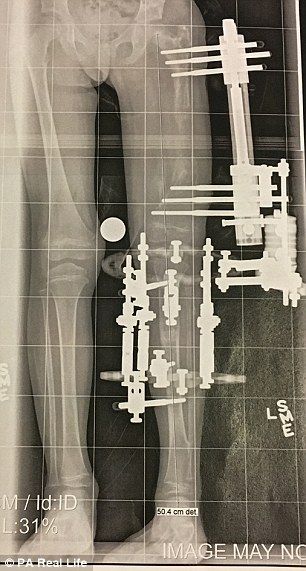

Contactó con el doctor Shawn, experto en discapacidades de este tipo, y decidieron someter a la menor a una complicada operación para alargar su pierna. Tras seis largas horas en quirófano, los médicos pudieron dar la noticia: habían conseguido reconstruir la cadera, el tobillo y la rodilla.

Así, Elsie consiguió andar con 21 meses, pero lo más duro vendría aún. Después de la cirugía, su madre se comprometió a activar manualmente los tornillos de la prótesis que le colocaron para separar el fémur y la tibia tres veces al día. Por tanto, fracturaron la pierna izquierda de la pequeña Elsie 300 veces a lo largo de cuatro meses, y consiguieron lo que pretendían, que la pierna corta se alargase 10 centímetros.